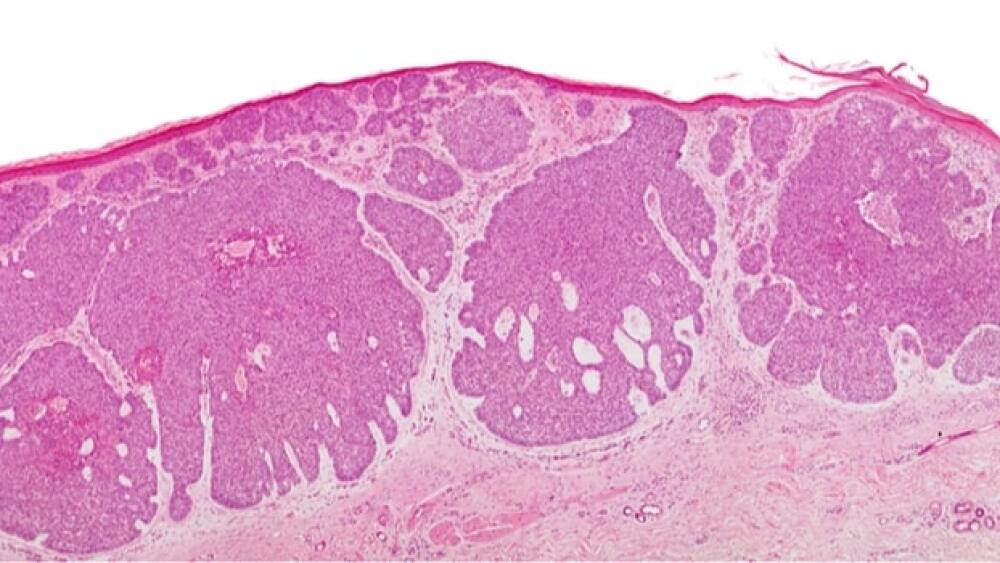

Basal cell carcinoma is a common type of non-melanoma skin cancer. While the vast majority of BCCs are caught early and easily cured with surgery and radiation, a small proportion of tumors can become advanced and penetrate deeper into surrounding tissues or spread to other parts of the body, which is more difficult to treat. In the U.S. alone, approximately 2 million new cases of BCC will be diagnosed every year, 20,000 U.S. patients will have advanced BCC and 3,000 patients are expected to die from this disease.